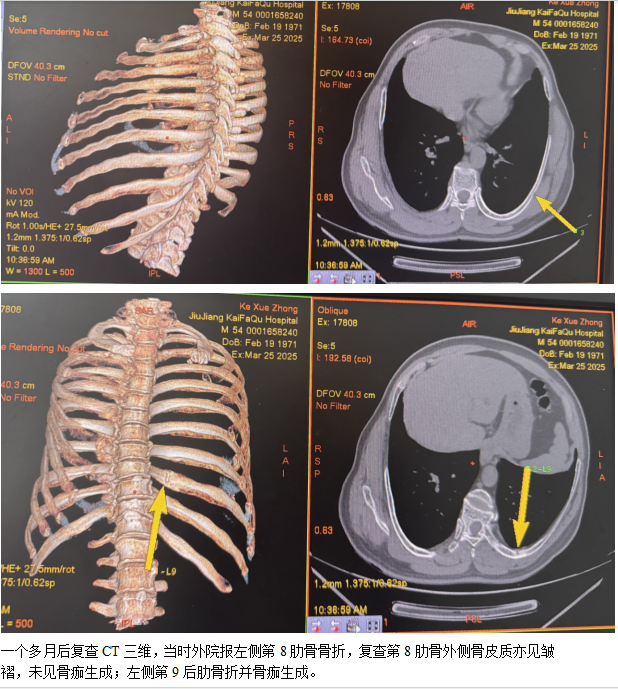

骨折后21 ~ 40 天,骨折断端骨内膜增生成骨,可见骨痂形成,大大提高隐匿性骨折的检出率,在多平面重组图像上可见部分骨痂形成,呈现云雾状稍高密度影,边缘较模糊。

骨折41 天后,骨折断端内外骨痂增生,新生骨逐渐增多,此时在多平面重组图像上密度亦随之增高。

而在50 天以后,骨膜反应逐渐消退,肋骨塑形,骨痂逐渐吸收、缩小,在多平面重组图像上所呈现肋骨骨折征象的敏感性逐渐降低。

因此结合首次检查,21 ~ 40 天为显示隐匿性肋骨骨折复查的最佳时间段。胸部外伤所致肋骨骨折大部分涉及事故责任认定、赔偿等问题,有无肋骨骨折、骨折数量确定至关重要;复查检出肋骨骨折多为不全性或隐匿性骨折,无严重并发症,但会对司法鉴定、赔偿及量刑产生影响,建议胸部外伤后当天和4-6周后复查一次肋骨CT检查。